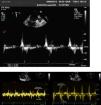

Anticoagulation after LAA electrical isolationLAAEI might cause electromechanical dissociation with the potential for thrombus formation. Two parameters, LA dilatation and low LAA emptying and filling velocities have remarkably been proven to be predisposing factors for smoke and thrombus formation.25 The LAA is a highly mobile and dynamic structure with distinct patterns of contraction and relaxation either in sinus rhythm or in AF. During sinus rhythm four waves are noted. The first wave starts in late diastole and represents rapid forward flow probably due to LAA contraction/emptying, this is followed by a second large retrograde wave that represents LAA filling. Then, additional forward and retrograde wave velocities are seen. These might be the result of ventricular relaxation and LAA elasticity, respectively (Figure 8A).26 It is important to recognize that these velocities are heavily dependent on loading conditions and left ventricular function.27 In our current practice TEE is performed six months post LAA ablation to assess the presence of a consistent A wave, LAA flow velocity, and LAA contractility. Patients with poor LAA velocity (<0.4 m/s) and/or abnormal LAA function are maintained indefinitely on oral anticoagulation regardless of the CHA2DS2-VASc score. In patients who remain in sinus rhythm with CHA2DS2VASc score of <2 in the LAA isolation group, and with adequate LAA flow velocity (>0.4 m/sec) and minimal smoke (Grade I-II) at the 3-month follow-up oral anticoagulation can be discontinued. In the BELIEF trial, no stroke or transient ischemic attack was reported in the LAAEI group, whereas 4 (4.5%) patients had stroke in the standard ablation group 2 (p=0.12).13 Similar results were observed by Yorgun et al. who used Cryoenergy for LAAEI. This study reported the LAAEI group only one ischemic stroke. This complication was observed five months after the procedure in a patient with CHA2DS2VASc score of 5, who had discontinued anticoagulation therapy for 10 days. Otherwise, LAAEI did not cause any other thromboembolic events despite the decrease in LAA flow velocities during the follow-up.17 Interestingly, although the LAA flow velocity usually decreases after isolation some patients maintain velocities within normal ranges (Figure 8B). Although, it seems counterintuitive that even though the LAA is electrically isolated, this structure can still contract. The exact mechanism of this phenomenon still remains to be elucidated. Rillig and colleagues28 reported that electrical isolation of LAA is associated with an increased incidence of LAA thrombus and stroke when compared to patient that did not undergo LAAEI. Nevertheless, all three patients who had a cerebral thromboembolic event had AF recurrence with one patient off NOAC, one patient on warfarin with subtherapeutic international normalized ratio at the time of the event, and one patient on dabigatran without verification of patient compliance. Moreover, that group also performed a more extensive approach to isolate the LAA with a wider area of ablation after PV isolation, which consisted in a posterolateral mitral isthmus line and an anterior line from the right superior pulmonary vein to the lateral mitral annulus in the majority of patients. This type of extensive ablation might have compromised the overall atrial contraction and could have become prothrombotic.28 We have reported data from 1854 consecutive AF patients receiving LAA isolation along with PVI. TEE at six months post-ablation follow-up showed impaired LAA mechanics in 58% of the patients. The overall thromboembolic event rate was 0.08% and 2.26% in on- and off-anticoagulation groups, respectively (p<0.001). Of the 14 patients with stroke, 12 (85.7%) had subtherapeutic warfarin level or discontinued their NOACs for more than 5 days. These results provide strong evidence that LAA isolation is not associated with a higher risk of thromboembolic events even in the presence of impaired LAA function as long as optimal oral anticoagulation is rigorously taken.29

Blood flow velocities measured by transoesophageal echocardiography in normal sinus rhythm. Top: Four distinct waves are seen. The first wave (1) starts in late diastole and represents rapid forward flow (0.62 m/s) probably owing to LAA contraction or emptying, followed by a second (2) large retrograde wave (0.42 m/s) that represents LAA filling. Two additional forward (3) and retrograde (4) wave velocities are then seen. These might be the result of ventricular relaxation and LAA elasticity, respectively. Bottom: Emptying and filling LLA velocities prior (left) and 6 months following radiofrequency ablation (right) of this structure in a patient with LSPAF. Note that velocity remained the same at 1 m/s.